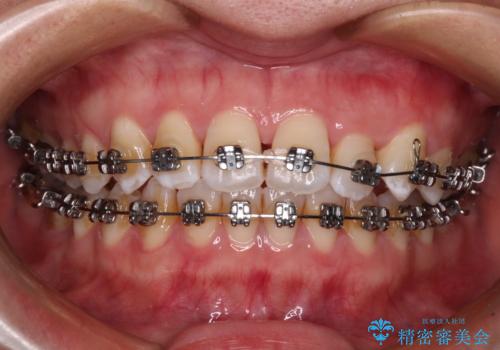

- メタルブラケット

上顎の拡大に伴い反対咬合があっという間に改善されました。

元々の歯列不整は軽微であったため、僅か1年の期間で治療を終えることができました。